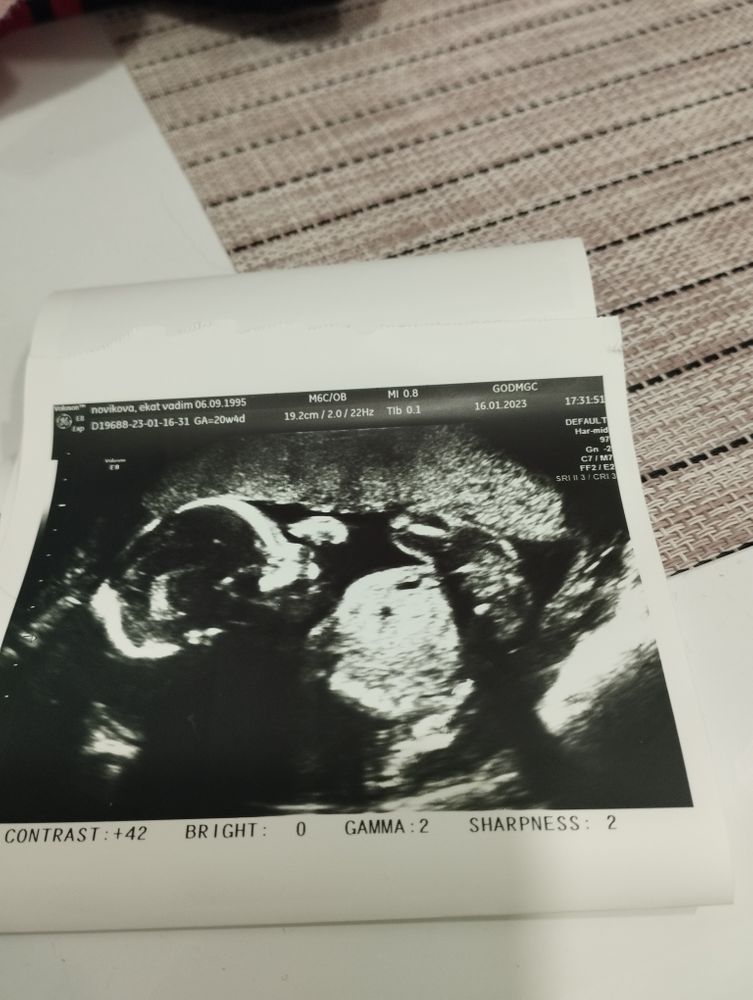

Но время неумолимо летит, и сегодня был наш второй скрининг!) Слава богу, всё отлично - даже шейка держится молодцом, 34 мм (после конизации на 1 скрининге была 24 🤨). И это без швов и пессария, только 200 Утрожестана на ночь.